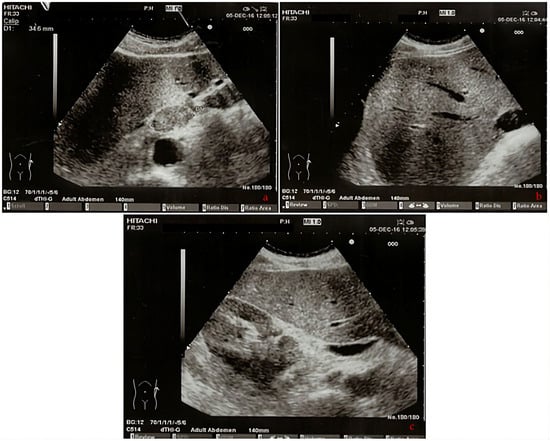

| 2016 | Patient presentation Diagnosis Abdominal ultrasound Total body CT scan  | Worsening non-productive night cough, no dyspnea. Metastatic lung cancer. Presence of malignant lymph nodes near the hepatic hilum. Solid nodular- like expansive process in the right upper lobe of the lung and multiple lymphadenopathies in the mediastinum and abdomen.  |